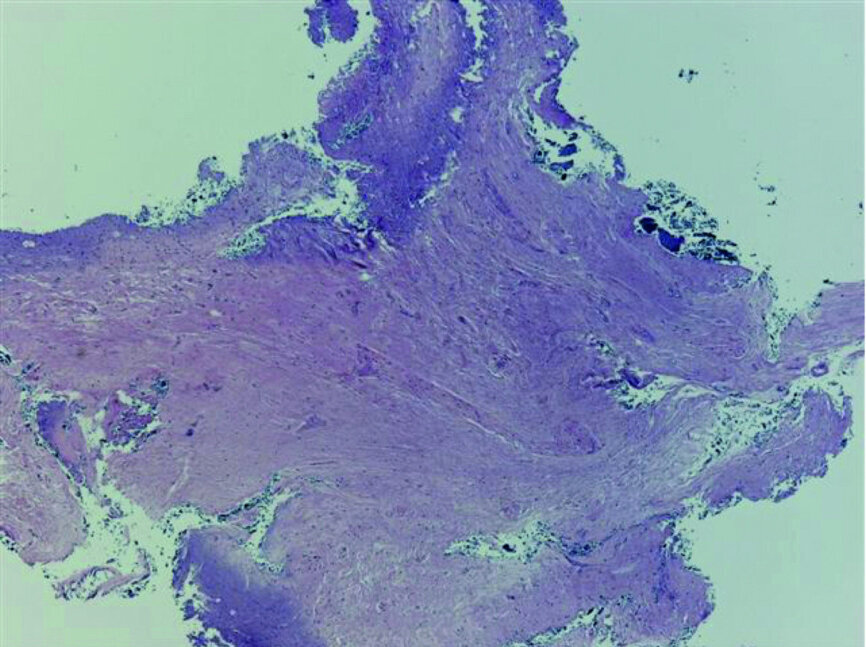

Fig. 20: Tissue removed from the endodontic space three months after transplantation (H&E stain; 2× magnification).

Fig. 21: Tissue removed from the endodontic space three months after transplantation (H&E stain; 4× magnification).

Pulp histology and necessity of endodontic treatment

Full development of the root can be expected when surgery is performed under ideal circumstances and Hertwig’s epithelial sheath is preserved; moreover, it depends on the root length at the moment of transplantation. [14] Teeth in the early stages of root development show less post-transplantation root growth than those with more mature roots, but incompletely formed apices. [15]Pulp regeneration and revascularisation are expected when the apical foramen displays at least a diameter of 1 mm radiographically. [16] Obliteration of the root canal is to be expected, owing to ingrowth of connective tissue. When roots are completely developed, root canal therapy is indicated. [17] In one of our cases, pulp histology was performed on the tissue extracted from root canals, and connective tissue with low vascularity was found (Figs. 20 & 21).